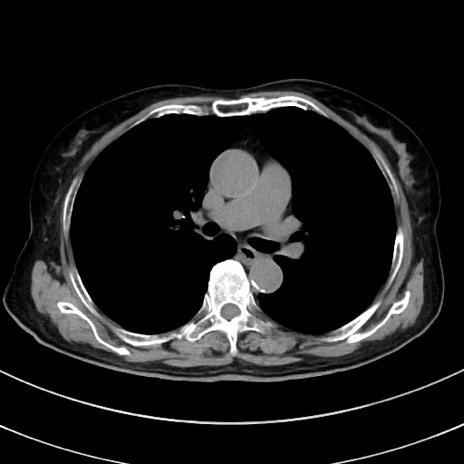

冠状断像

【症例】70歳代 女性

【主訴】心窩部痛

【現病歴】延髄病変の精査・加療にて神経内科入院中。本日より心窩部痛あり。

【身体所見】右下腹部を中心に圧痛と反跳痛あり。

【データ】WBC 10900、CRP 0.02